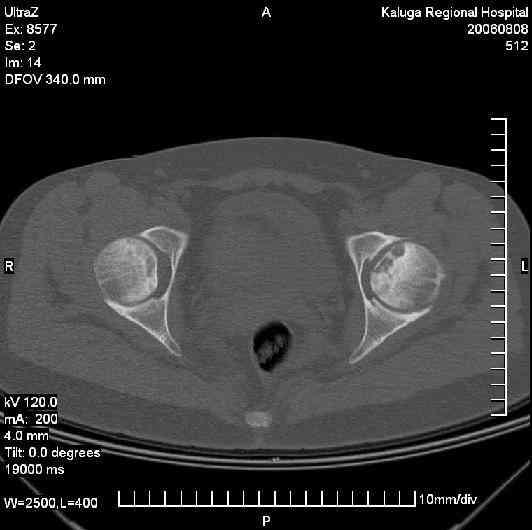

Уважаемые коллеги! Подскажите как быть? Моя родственница и одновременно пациентка(30 лет) выполнила по поводу болей в тазобедренном суставе КТ.

Боли по нарастающей беспокоили в течении 2 лет. Клинически имеет место прихрамывание и незначительное ограничение отведения.Подход к проблеме в детстве приблизительно ясен. Как быть в данном случае?Процесс развивается и на контрлатеральной стороне.Фото прилагается.